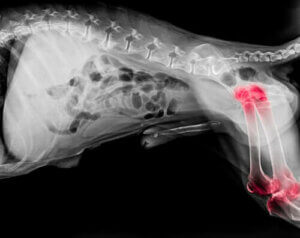

전문가들은 반려견 5마리 중 1마리가 관절염으로 고통받는다고 추정한다. 관절 문제는 모든 나이대에서 나타나지만 노견의 발병률이 높은 편이다. 관절염은 팔꿈치와 어깨 관절 모두에 염증을 일으키는 퇴행성 질환이다.

관절염을 앓는 반려견은 특별 관리와 주의를 필요로 한다. 퇴행성 질환이기 때문에 통증과 질병의 진행 속도를 늦추기 위한 완화 치료가 가장 효과적이다. 정형외과용 매트리스나 관절 보호대처럼 반려동물의 웰빙을 향상할 수 있는 방법이 많은데 반려견의 식단 조절도 도움이 될 수 있다.